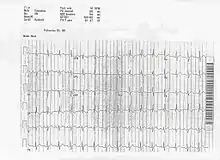

On ECG a left axis deviation is generally found in ostium primum ASD, but an RSR pattern (M pattern) in V1 is characteristic. Fixed splitting of the second heart sound (S2) occurs because of equal filling of the left and right atria during all phases of the respiratory cycle.

Patients with atrial Septal Defects may have atrial fibrillation, atrial tachycardia, or atrial flutter, but these abnormal heart rhythms are not usually seen until the affected individual grows older. Features also seen on the ECG include right atrial enlargement and varying degrees of atrioventricular block. When a person is suspected of having an ASD based on the findings of an incomplete right bundle branch block with a rSr' or rSR', the frontal plane QRS should be examined. The frontal plane QRS is the most helpful clue to distinguish between an ostium secundum ASD and an ostium primum ASD. In primum defects left axis deviation is seen in most patients with an axis of > -30 degrees and very few patients have right axis deviation. In contrast ostium secundum defects have an axis between 0 degrees and 180 degrees with most cases to the right of 100 degrees.

In the ECG above, you can see an example of the rSR' pattern in V1 with a R' greater than S with T wave inversion which is commonly seen in volume overload right ventricular hypertrophy.